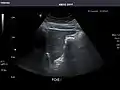

Right kidney

Left kidney

Kidneys: Right and left kidneys measure 11.5 cm and 12 cm in length respectively. No hydronephrosis. Small left lower pole kidney cyst.